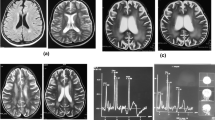

A 42-month-old Chinese boy (bodyweight, 16 kg; height, 102 cm) was admitted to the Department of Nephrology and Immunology of our hospital due to edema and proteinuria. He underwent laboratory examination for macrocytic anemia (hemoglobin, 58 g/L), proteinuria (2+) and hematuria (103/HP). The 24-h urinary level of microprotein increased to 75.7 mg/24 h (reference range: 2.6–16.6 mg/24 h). Anemia, proteinuria, and hematuria continued after infusion of washed red blood cells (RBCs), methylprednisolone administration, and anti-infection treatment after hospital admission. Ten days later, he suddenly developed frequent convulsions and persistent hypertension. He was transferred to the intensive care unit for tracheal intubation, and methylprednisolone pulsation treatment (300 mg/d for 3 days followed by gradual reduction) and symptomatic treatment. The convulsions ceased and hypertension was relieved, but anemia, proteinuria, and hematuria persisted. Renal biopsy was done. Under light microscopy, diffuse membranoproliferative lesions of the glomerulus were noted. Also, changes in congestion of glomerular capillary loops, some degeneration of tubular epithelial cells, and intraluminal protein casts were documented (Fig. 1). Immunofluorescence analyses showed diffuse granular deposition of immunoglobulin M (IgM; 3+), C1q (+) and fibrinogen (+) along the glomerular mesangium and capillary loops (Fig. 2). Screening of amino acids and acyl carnitine in blood showed that the propionyl carnitine:acetylcarnitine ratio increased to 0.29 (reference range: 0.02–0.25). Also, profiling of organic acids in urine by gas chromatography–mass spectrometry revealed increased levels (in μmol/L) of methylmalonic acid (81.9; reference range: 0.0–4.0) and methyl citrate (0.9; 0.0–0.8). Further detection suggested the homocysteine content in blood to be > 100 μmol/L (reference range: 0.0–15.0 μmol/L). The level of vitamin B12 was normal (263.4 pg/mL; reference range: 200.0–900.0 pg/mL). Comprehensive genetic analyses of peripheral blood-derived DNA revealed compound heterozygous variants of the methylmalonic aciduria type C and homocystinuria (MMACHC) gene, which suggested the diagnosis was Methylmalonic Acidemia and Homocystinuria (cblC type) (Table 1; Fig. 3).

After hospital admission, he was treated with neurotrophic drugs, but symptoms were not alleviated. Routine, biochemical, culture and autoimmune encephalitis antibody in cerebrospinal fluid were normal. Electroencephalography was normal. The T1-weighted imaging (T1WI) sequence of cranial magnetic resonance imaging (MRI) showed decreased signals for the clivus and cranial barrier. T1WI and T2WI sequences of MRI showed uniform reduction of signals in the whole spinal column, centrum and accessories. Screening for amino acids and acyl carnitine using blood samples revealed the level of propionyl carnitine (15.46 μmol/L; reference range: 0.38–3.6 μmol/L) and the ratio of propionyl carnitine:acetylcarnitine (0.48; reference range: 0.04–0.22) to be increased. Also, profiling of urinary organic acids by gas chromatography–mass spectrometry showed high levels (in μmol/L) of 3-hydroxypropionic acid (13.07; reference range: 0.0–1.1) and methylmalonic acid (50.82; 0.2–3.6). The homocysteine concentration in serum was 85.6 μmol/L (reference range: 0.0–15.0 μmol/L). The level of vitamin B12 was the lower limit of normal (231.2 pg/mL; reference range: 200.0–900.0 pg/mL). Genetic analyses of peripheral blood-derived DNA was undertaken and showed compound heterozygous variants of the amnionless (AMN) gene (Table 2) and suggested the diagnosis of Imerslund–Gräsbeck syndrome (IGS). After 1 week of treatment comprising L-carnitine (3 g/day, p.o.), vitamin B12 (1 mg/day, i.m.), vitamin B6 (30 mg/day, p.o.), folic acid (5 mg/day, p.o.), coenzyme Q10 (10 mg/day, p.o.) and betaine (3 g/day, p.o.), the level of homocysteine in blood and methylmalonic acid in urine decreased to normal ranges. The hemoglobin level increased gradually and remained stable, but proteinuria and unsteady walking persisted. The amino acids and other metabolites in blood and urine were measured regularly, and the dose and frequency of drugs adjusted according to the results. After 4 months, the patient still had proteinuria (2+) and then was lost to follow-up.